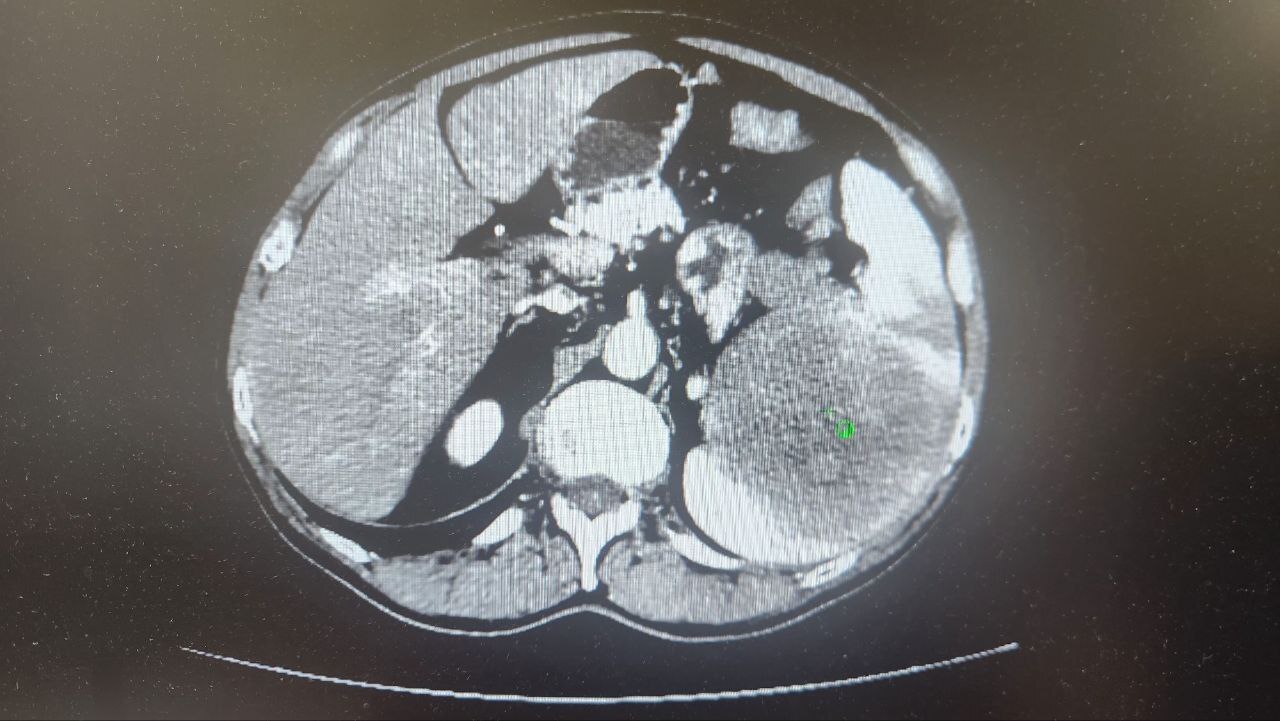

Опухоль нашли у 69-летнего туляка на плановом УЗИ брюшной полости. Дальнейшее обследование подтвердило диагноз: опухоль поразила селезенку, лимфоузлы и хвост поджелудочной железы.

Врачи приняли решение об удалении единым блоком селезенки, части поджелудочной железы с опухолью и пораженными лимфоузлами с использованием лапароскопического метода.